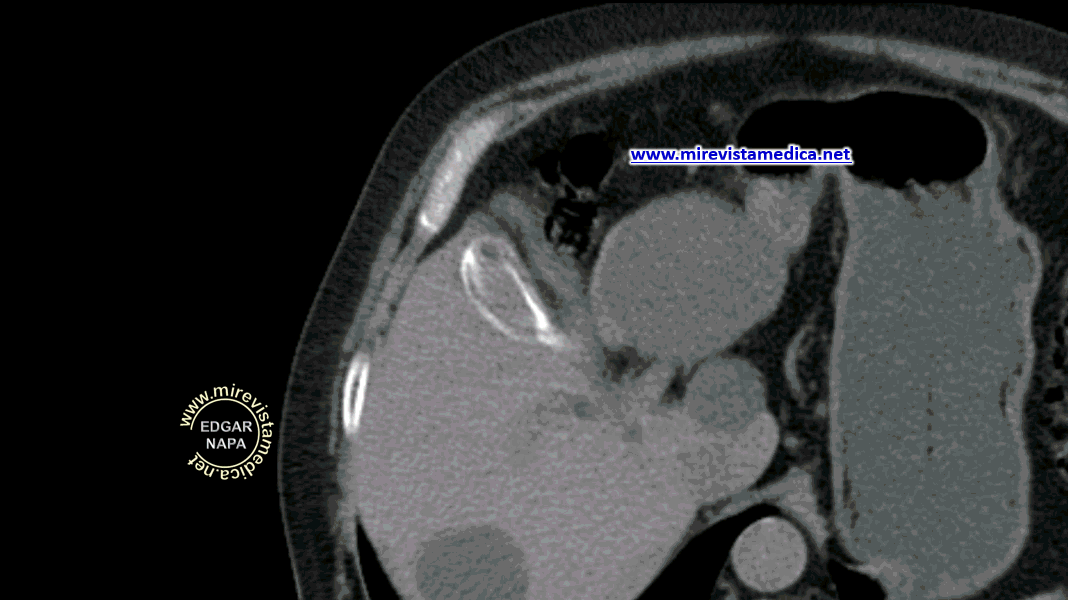

Tomografía abdominal, con contraste , muestra la pared hiperdensa que delimita su silueta.

Tomografía abdominal, con contra ste, muestra imagen hiperdensa en la fosa vesicular. en relació n con vesícula de paredes calcificada.